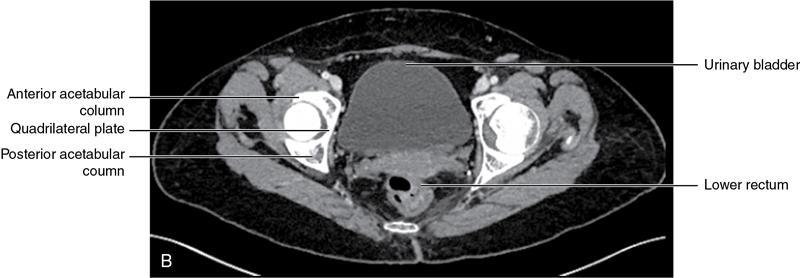

CROSS SECTIONAL ANATOMY OF ABDOMEN Satya Jha NORMAL ANATOMY OF ABDOMEN AND PELVIS Amandeep Singh The two major surfaces: The anterior and posterior layers of the coronary ligament converge on bare area (not covered by peritoneum). Its right and left margins form the right and left triangular ligaments. The right triangular ligament extends toward the diaphragm and separates right subphrenic space from right subhepatic space. The left triangular ligament gives tracts extending to the diaphragm and falciform ligament and does not compartmentalize the left subphrenic space. Ligamentum teres or the obliterated umblical vein is contained in falciform ligament which attaches the liver to anterior abdominal wall. The main portal vein, the proper hepatic artery and the common bile duct are contained within investing peritoneal folds of hepatoduodenal ligament at the porta hepatis (Fig. 7.2.2.1). Liver is divided into eight segments which are functionally independent and have their own vascular supply and biliary drainage. Arterial circulation: The branches of the hepatic artery accompanying the portal veins. Hepatic venous system: The right, middle, and left hepatic veins draining into IVC (Figs. 7.2.2.2 and 7.2.2.3). The gallbladder is a blind pear-shaped muscular membranous sac which is an embryologic derivative of the foregut, is a pouch lying along the undersurface of the liver. The gallbladder fossa is located in the plane of the interlobar fissure, which lies between the right and left hepatic lobes. Its major function is to store and concentrate bile which is produced by the liver. It measures approximately 4 cm in diameter when it is normally distended. Gallbladder is a smaller tubular structure in contracted state. The normal gallbladder wall thickness ranges from 1 to 3 mm. The gallbladder is divided into the fundus, body and neck. Infundibulum is present in the region of neck of the gallbladder, which is called the Hartmann pouch, where gallstones are usually impacted. Intrahepatic biliary radicles (IHBRs) scattered throughout the liver get confluent towards the hilum. They unite to form the right and left main hepatic ducts which further unite to form common hepatic duct (CHD) at the hilum. Common bile duct is formed by the union of cystic duct with common hepatic duct. The main pancreatic duct is joined with the common bile duct to form the ampulla of Vater at the major duodenal papilla (Figs. 7.2.2.4 and 7.2.2.5). Pancreas is located in anterior pararenal space of retroperitoneum anterior to perirenal (Gerota’s) fascia and posterior to parietal peritoneum. It is divided into head, uncinate process, neck, body and tail from right to left. Pancreas lies anterior to portal vein, which marks the point of transition between the body and neck. The region between head of pancreas and second and third parts of duodenum is known as the pancreatic groove. In postnephrectomy cases or with agenesis of kidney or ectopic kidney, pancreas moves posteriorly to partially fill in the empty renal fossa; its soft tissue density should not be mistaken for recurrent tumour. It is located in the pancreatic groove and is bounded superiorly by the duodenal bulb, laterally by second portion of duodenum, inferiorly by third portion of duodenum, medially by superior mesenteric vein and anterior to inferior vena cava. It is a wedge or wedge shaped lying posterior to superior mesenteric artery and vein. It is an imaginary junction between the head and body and lies directly over the junction of the splenic vein and superior mesenteric vein. It is located posterior to the lesser sac and anterior to the aorta, left adrenal gland, left kidney, and renal vessels and runs obliquely upward to the left of the superior mesenteric vessels. It is situated median to the colonic flexure and anterior to the left kidney. It is located in close proximity to the splenic hilum without a notable relation with the body of pancreas. It is seen anterior to the left kidney and median to the colonic flexure. The distal part of the tail passes between the peritoneal layers of the splenorenal ligament (Fig. 7.2.2.6 and 7.2.2.7).